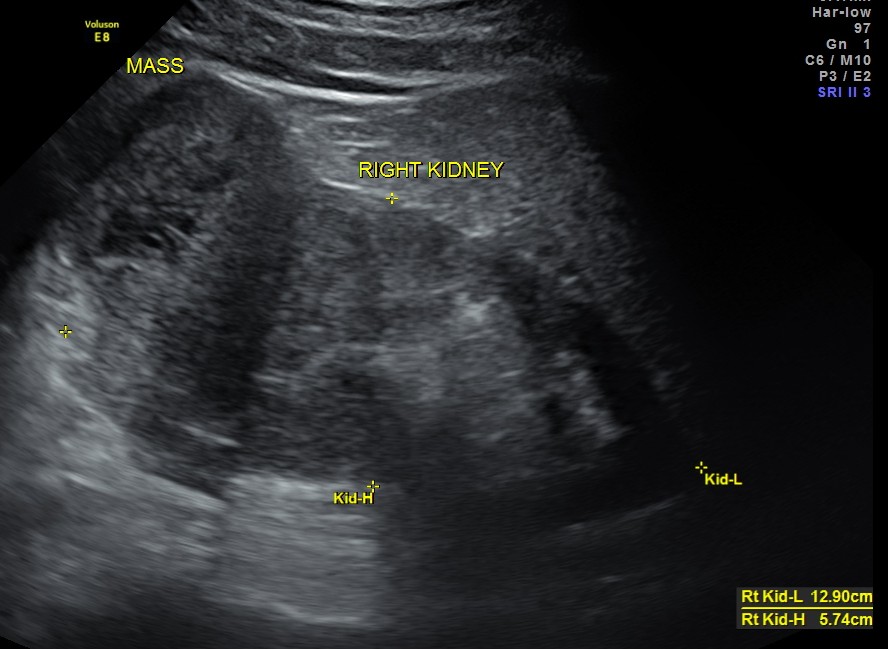

The right kidney pictures are given below. Mass lesion seen in the lower pole .